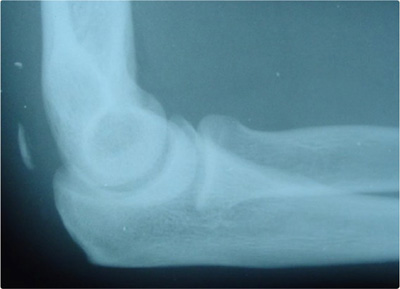

- It’s important to distinguish a triceps tear from an olecranon fracture which also causes a loss of elbow extension. This can be detected with physical exam and x-rays. For this reason xrays are tpyically obtained when evaluating a triceps injury

- Lateral elbow x-ray may show avulsed proximal humeral bone if an avulsion injury occurred, known as a ‘fleck’ sign.1 However, if no avulsion is present, the x-ray will appear normal.